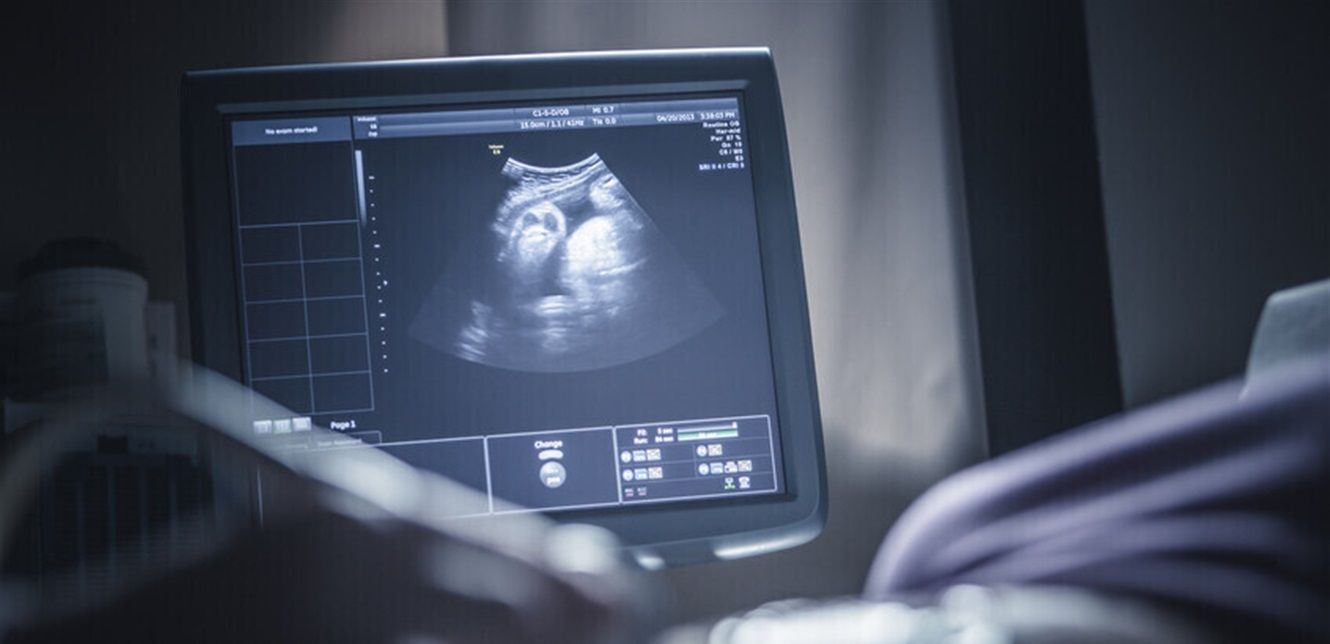

كشف علماء أن تقدم عمر المرأة هو العامل الأساسي والمباشر وراء توقف تطور الأجنة.

وشملت هذه الدراسة التي نشرتها مجلة Aging-US العلمية، تحليل بيانات 25974 جنينا من 1928 دورة تلقيح اصطناعي، مع التركيز على الحالات التي تتمتع بفرص نجاح عالية.

وأظهرت النتائج أن نسبة توقف تطور الأجنة ترتفع بشكل ملحوظ ومتسق مع تقدم عمر الأم، حيث تصل هذه النسبة إلى 33% لدى النساء تحت سن الـ35، بينما ترتفع إلى 44% لدى النساء فوق 42 سنة.

والأهم من ذلك، أن الدراسة كشفت أن معدل التشوهات الكروموسومية لم يظهر ارتباطا قويا بمعدلات توقف التطور الجنيني بعد الأخذ في الاعتبار عامل العمر. (روسيا اليوم)